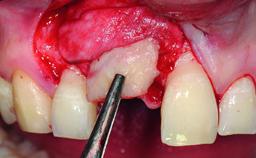

A healthy 38-year-old male patient was referred for replacement of a failing tooth-supported cantilever fixed dental prosthesis on teeth 11 and 21. The patient reported a history of trauma at 13 years of age that had resulted in the subsequent loss of tooth 11, as well as endodontic treatment of the adjacent abutment tooth 21. A metal-ceramic cantilever fixed dental prosthesis replacing tooth 11 had been provided by his general dentist several years after the loss of the tooth, with tooth 21 as the sole abutment. At the time of initial presentation, this restoration had been in service for over 20 years.